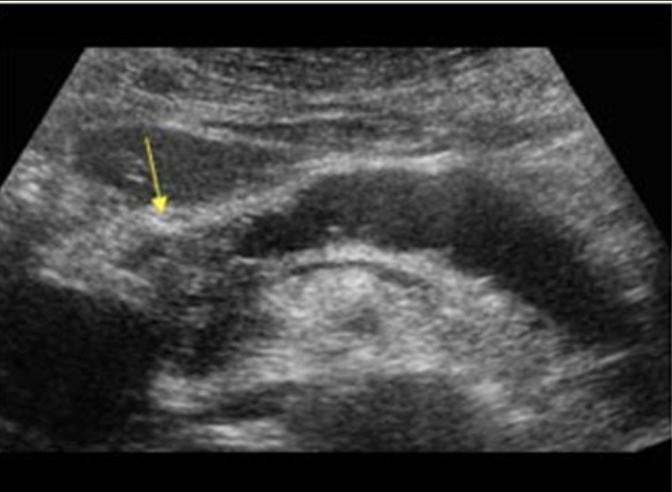

Hydronephrosis → dilation of renal collecting system from mechanical obstruction or functional dysfunction (calculi, mass, trauma, pregnancy)

2D US: grade 1 (mild) → pelviectasis, cortex preserved, grade 2 (mild to moderate) → expands into major calyces, cortex preserved, grade 3 (moderate) → expand all calyces, entire pelvis dilated, cortex preserved, grade 4 (severe) → cortical thinning, AKI to CKD, creatinine >1.2

color doppler: avascular

DDX: parapelvic cysts